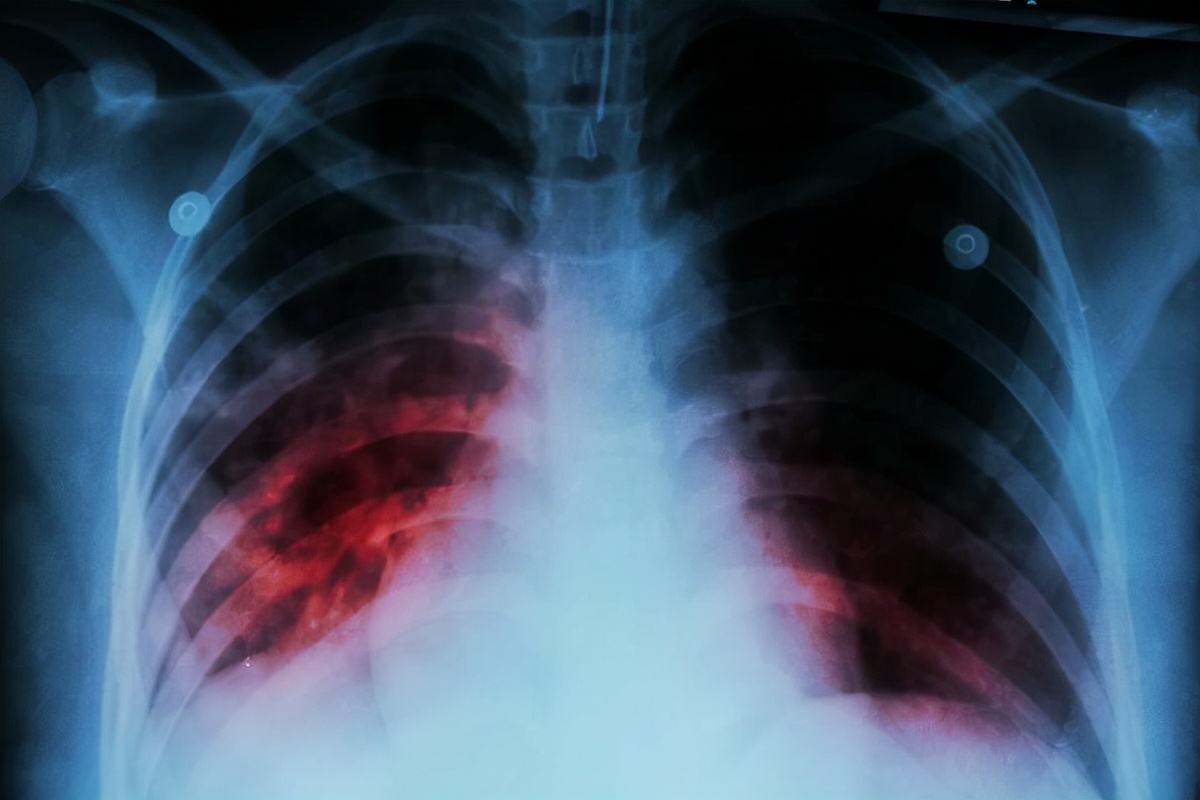

三、肺结核

如果胁肋部位出现疼痛感的时候,患者还伴有反复咳嗽、胸痛、午后发烧、夜晚盗汗现象,一般与患上肺结核有关。肺结核是一种因为感染了结核杆菌所引起的呼吸系统疾病,有着较强的传染性。

一旦患上肺结核,患者除了表现出咳嗽、咳痰、胸痛以及盗汗、身体疲乏等症状之外,炎症还会散播到胸膜部位,导致胸膜受到刺激,就会引起胸部疼痛,以及肋骨部位疼痛现象。

一旦引发了肋骨结核并发症的话,这种胁肋部位疼痛的症状会特别明显,并且会伴有咳血的现象。